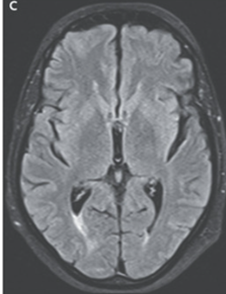

シクロスポリンを中止し、1週間後MRI再評価。改善が確認された。